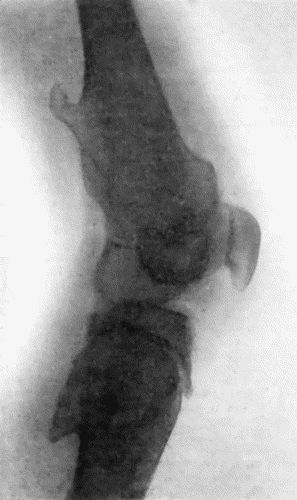

162.Bones of Knee in Charcot's Disease 533

163.Charcot's Disease of Left Knee 534